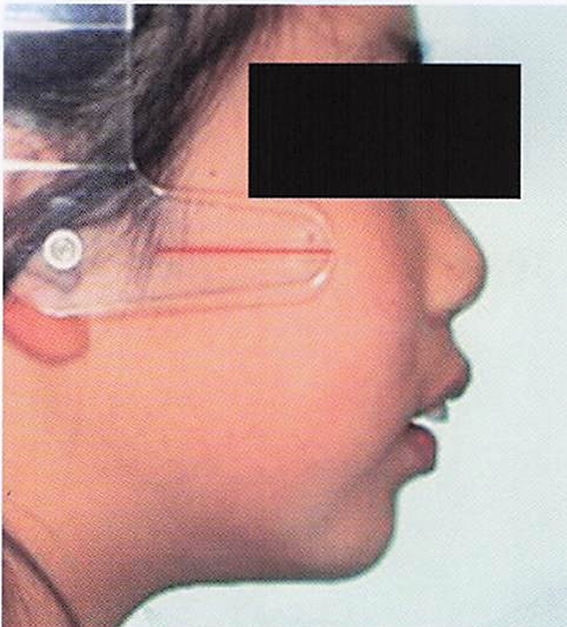

午前-55

10歳の女児。上顎前歯の歯ならびが気になることを主訴として来院した。 顔面写真、口腔内写真および治療に用いた装置の写真を別に示す。 期待できる効果はどれか。1つ選べ。

a.下顎前歯の唇側移動

b.下顎骨の前方成長促進

c.上顎大臼歯の近心移動

d.上顎骨の前方成長抑制

解答を見る

d